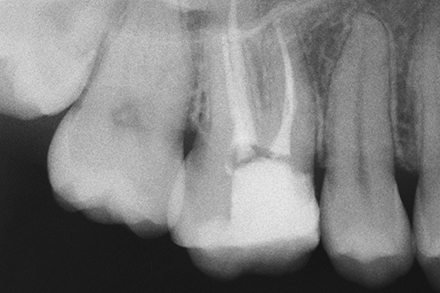

Tooth with new RCT in place.